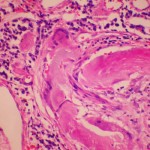

Publicado el año pasado en la revista Science, los resultados señalaron el interés internacional, incluyendo el Wall Street Journal y la cadena CNN. La FDA originalmente aprobo el bexaroteno para el tratamiento de linfomas de las células T cutáneas de una forma de cáncer de piel en 1999, pero Landreth, director del Laboratorio de la Facultad de Medicina de Alzheimer Research, Cramer y sus colegas encontraron que el medicamento elimina significativamente la beta amiloide, una proteína implicada en el desarrollo de la enfermedad de Alzheimer cuando se acumula en el cerebro.

Los investigadores demostraron que una dosis de bexaroteno (un receptor agonista de retinoide X (RXR) ) elimina la acumulación de beta amiloide por el 25 por ciento en las primeras seis horas, un efecto que duró hasta tres días.